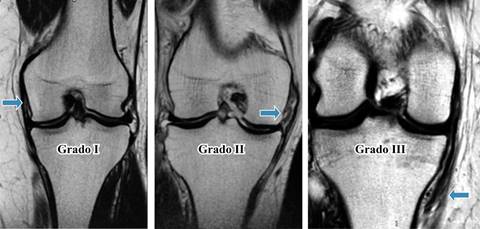

Las lesiones del LCM según la Asociación Médica Americana (AMC por sus siglas en inglés), se dividen en tres grados: el grado I se presenta con hipersensibilidad, pero sin hiperlaxitud. El grado II se manifiesta con sensibilidad localizada y desgarro parcial del LCM y de las fibras oblicuas del ligamento posterior, las cuales continúan opuestas, puede existir laxitud no patológica. En el grado III las fibras tienen una disrupción completa y existe hiperlaxitud al aplicar una fuerza en valgo. Esta clasificación puede ser subjetiva, ya que depende de la capacidad de relajación del paciente y la capacidad del médico para aplicar la fuerza en valgo.1,7 También se pueden clasificar radiológicamente cuando se compara la apertura medial de la articulación contra la extremidad contralateral. El grado I presenta una diferencia de 3 a 5 mm, el grado II va de 6 a 10 mm y el grado III con una diferencia > 10 mm.

EL método de valoración en resonancia magnética que se utilizó fue de acuerdo a la clasificación internacional de lesiones de ligamento medial10 (Tabla 1).

Tabla 1: Clasificación internacional de lesiones de ligamento colateral medial de la rodilla.

| Grado | Lesión | IRM |

|---|---|---|

| I | Ruptura microscóscopica del lig, sin inestabilidad. Tensión y dirección conservadas con líquido periligamentario | Hipointenso en T1 e hipertenso en T2 y sat grasa |

| II | Ruptura parcial de las fibras menor de 80%. Existe edema asociado a partes blandas, periligamentarios e inestabilidad | Hipertensas en sec T1, T2 y Sat. Grasa |

| III | Ruptura de las fibras mayor de 80% | Intensidad de señal de las fibras suele estar retardas |

IRM = imagen de resonancia magnética.

Tuvimos 37 casos (56.9%) de género masculino y 28 casos (43.1%) femeninos, la edad promedio de los pacientes fue de 45.64 años (con un rango de 19-80 años), existía un predominio de lateralidad mayor del lado izquierdo con 38 casos (58.46%). Las lesiones encontradas de grado I fueron en 49 casos (75.38%), de grado II, 10 casos (15.38%) y de grado III, se detectaron dos casos (3.07%), se presentaron cuatro casos (6.15%) de tendinosis del LCM (Figura 1). Las lesiones asociadas halladas fueron lesiones del menisco medial en 30 casos (46.15%), de las lesiones condrales juntas se hallaron 24 casos (36.91%), de fémur fueron 11 casos (16.92%), lesión condal de tibia en nueve casos (13.84%) y lesiones condales de la rótula en cuatro casos (6.15%), lesión del LCA en 20 casos (30.76%), la contusión ósea se observó en 12 casos (18.46%), de la lesión de vasto medial y lesión del retináculo medial se encontraron en nueve casos cada una (13.84%), la lesión del vasto lateral en seis casos (9.23%) y la lesión del LCP en cuatro casos cada una (6.15%), la lesión del menisco lateral y la tenosinovitis de la banda iliotibial se observaron en tres casos (4.61%), fractura de avulsión de la faceta medial y la tenosinovitis de la Pes Anserinus en dos casos (3.07%) y las lesiones del vasto medial, del cuádriceps, lesión del tendón poplíteo, tendón patelar, ruptura del semimembranoso, de la cápsula articular así como las fracturas de la cabeza del peroné y del polo inferior de la patela sólo se encontraron en un caso (1.53%) cada uno. Sólo se detectaron dos casos (3.07%) que presentaban exclusivamente una lesión aislada del ligamento colateral medial y fueron uno de grado I y uno de grado II respectivamente.

En nuestro estudio pudimos observar que tenemos una prevalencia de las lesiones del ligamento colateral medial por imagen en 17.66%. Una debilidad del estudio es que no fue posible determinar los antecedentes deportivos, su nivel de actividad física y mecanismo de lesión. Sabiendo que es una de las lesiones que más frecuentemente se asocia a deportes de contacto, en nuestra serie de casos se observó que 75% de las lesiones del LCM eran grado I, seguidas de 15% de grado II y 3% de grado III, muy parecida a la obtenida por Roach y colaboradores.

Para la valoración imagenológica del ligamento colateral medial, la mejor adquisición es la proyección coronal, la cual nos permite valorar la morfología, intensidad de señal, tensión, dirección y la inserción tibial y femoral. El ligamento colateral medial o ligamento colateral interno se observa hipointenso en todas las secuencias.